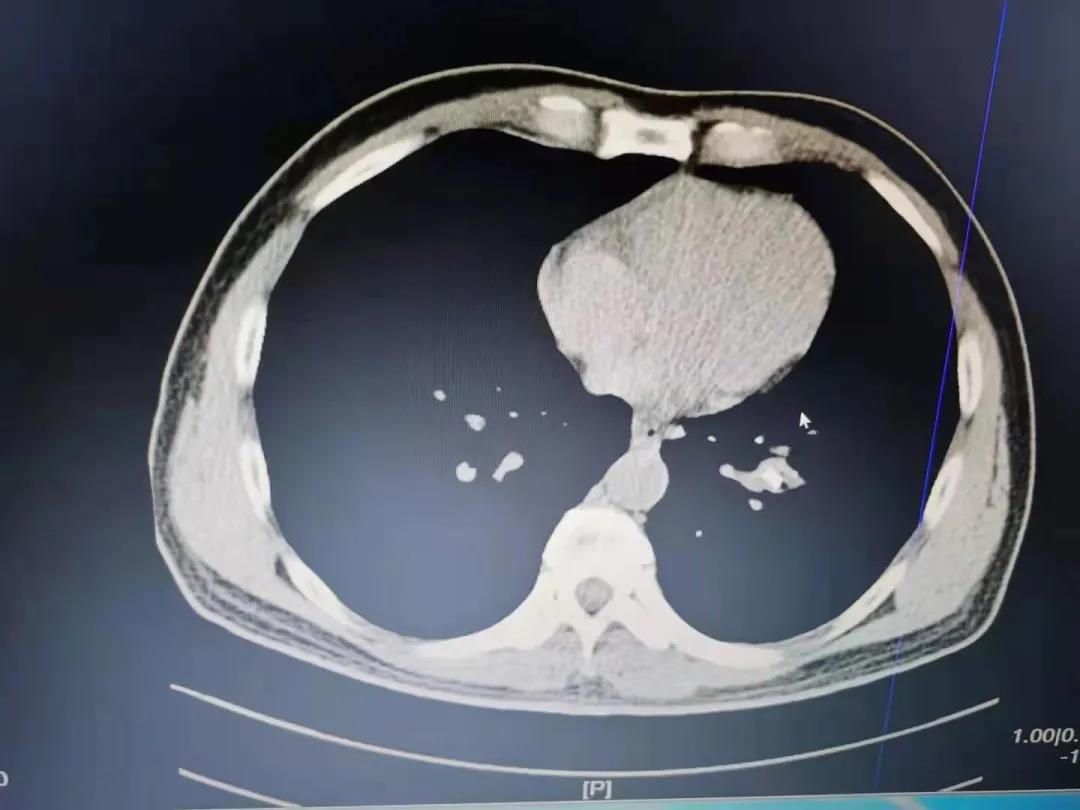

患者因“反复咳嗽1年余”就诊,查阅患者3年前的胸部CT片提示左下叶基底段高密度影,未予治疗。门诊完善胸部CT提示左下叶外后基底段支气管腔内异物并阻塞性肺炎。拟诊“1.支气管异物2.阻塞性肺炎”收入院,完善术前相关检查,排除支气管镜检查及治疗的禁忌症。考虑异物堵塞时间过长,有堵塞性肺不张,同时异物会刺激肉芽组织生长,经讨论后决定先行支气管镜检查。第一次进镜可见左下叶外后基底段支气管开口处大量的肉芽组织生长,触之易出血,异物完全被肉芽组织包裹,吸出大量粘稠分泌物,分泌物涂片见大量白细胞。考虑盲目取出异物,出血风险极高,决定抗炎1周后复查。